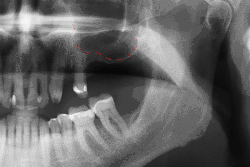

- с помощью рентгенографии изучаются качество и плотность костной ткани;

При утрате одного или нескольких зубов костная ткань в этом месте со временем истончается из-за отсутствия жевательной нагрузки, что ведёт к деформации челюстно-лицевой системы. Наличие имплантата обеспечивает адекватную нагрузку на кость челюсти подобно естественному корню зуба, поэтому истончения костной ткани не происходит. Каждый человек, который потерял один или несколько зубов в результате различных травм, болезней или разрушения зубов, имеют показания для имплантации зубов. Люди преклонного возраста также могут пройти процедуру имплантации, поскольку определяющим фактором её осуществления является скорее состояние здоровья, нежели возраст. Вопрос о том, возможно ли проведение дентальной имплантации, решается специалистом — стоматологом после тщательного медицинского обследования конкретного пациента и детального осмотра состояния его зубов.